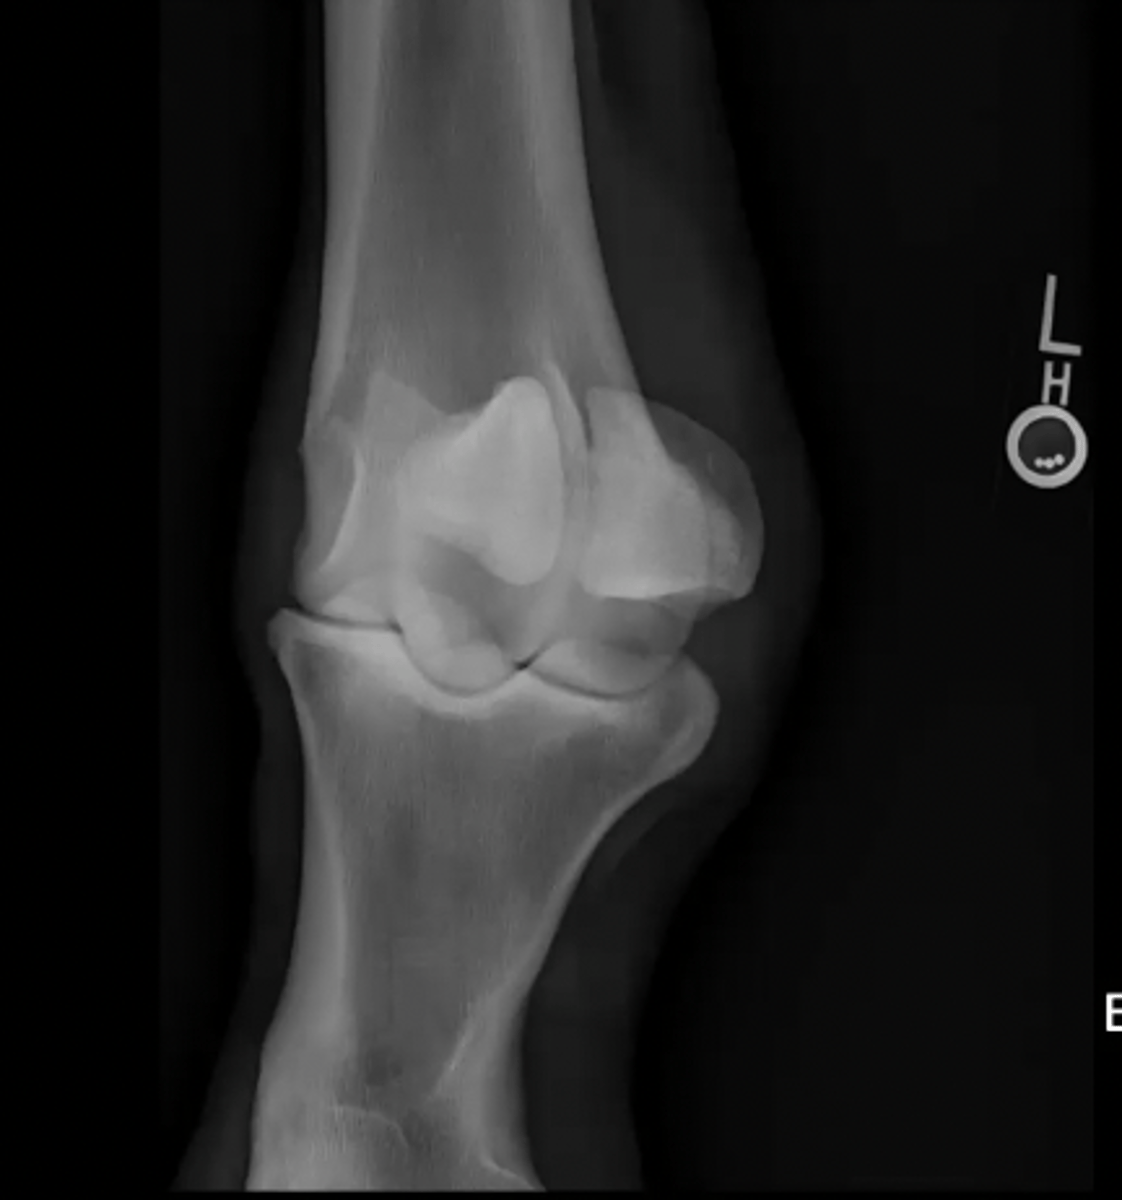

craniocaudal canine elbow

What is the view of this image?